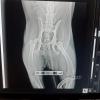

Emon omistaja ei kuitenkaan pennuista pahemmin piitannut ja vaikka pentuja ruokittiinkin, ne kulkivat ulkona vapaina. Paikalliset eläinsuojelijat kiinnittivät huomiota koiraperheeseen ja ne tulivat näille tutuiksi kuukausien kuluessa. Kaikki kolme pentua olivat narttuja ja jotta alueella ei pian eläisi kokonainen koiralauma, eläinsuojelijat käyttivät tytöt sterilisoitavana Viipurin koirien tukemassa SpayDay-tapahtumassa helmikuussa 2022. Koirat oli kuitenkin pakko palauttaa samaan paikkaan, sillä koteja tai hoitopaikkoja ei ollut tarjolla. Mieltä varjosti kuitenkin jatkuva pelko siitä, kuinka ne pärjäisivät. Lopulta kävi, kuten pelättiin, ja kaksi kolmesta loukkaantui. Kiran osaksi tuli vaikea lonkan sijoiltaanmeno, joka oli mahdollisesti seurausta törmäyksestä auton kanssa. Kira kinkkasi rampana pitkin tienvieriä, eikä sen jalka kestänyt lainkaan painoa. Kävi selväksi, että sitä oli autettava. Video Kirasta loukkaantuneena on nähtävissä täällä: https://youtube.com/shorts/gYHnmiy1tGA?feature=share

Kira pääsi hoidettavaksi eläinklinikka Aurikaan, jossa sen lonkka operoitiin. Kiran jalka ei tule klinikan lääkärien mukaan palaamaan koskaan täysin ennalleen, vaan pientä ontumista on luvassa pysyvästi. Tottumaton silmä ei ontumista kuitenkaan juuri huomaa. Kira saattaa tarvita fysioterapiaa ja kipulääkitystä myöhemmin elämässään, joten se adoptoidaan erityisadoptiona. Jalka kestää nyt kuitenkin painoa ja Kira ulkoilee mielellään.